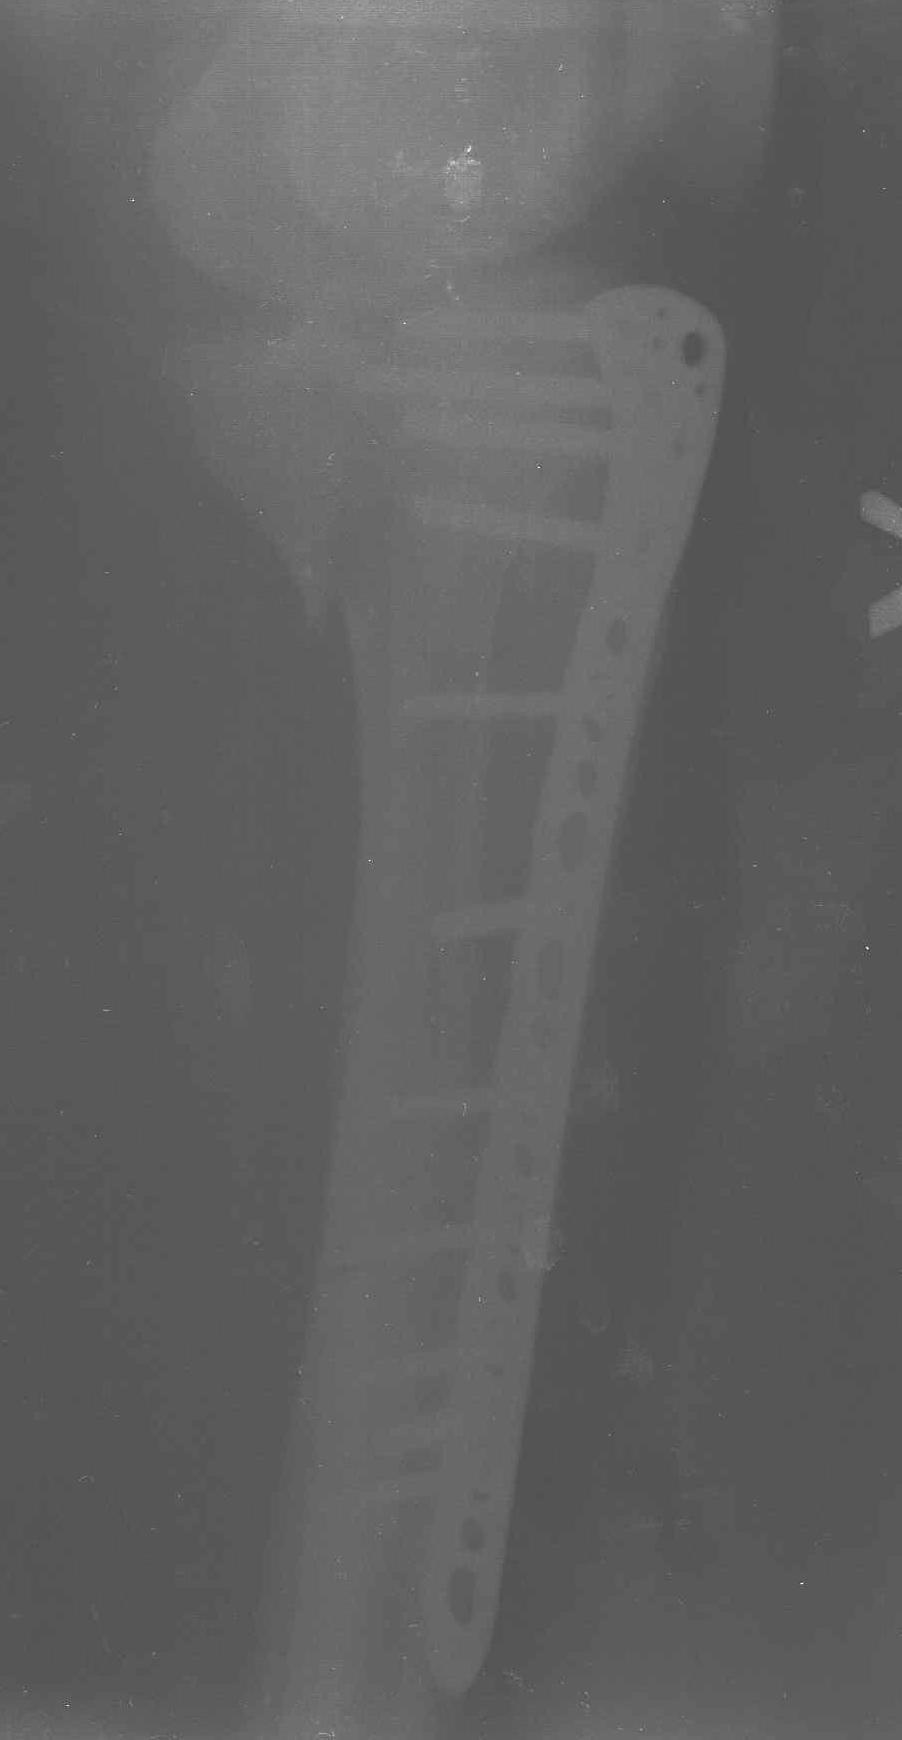

Такая ситуация характерна для многих, когда принимается ошибочное решение, т.е пытаются фиксировать одним имплантом переломы двух мыщелков. Латеральная пластина приемлема только для тех случаев, когда сохраняется интактным медиальный диафизарный кортекс и отсутствует фрагментация на верхушке медиального перелома.

Здесь как раз тот случай, когда результат зависит не только от мастерства хирурга, но и от наличия современных методов исследования. Например, КТ которая поможет рассчитать направления шурупов и установку импланта. Кроме этого, поможет определиться с доступом.